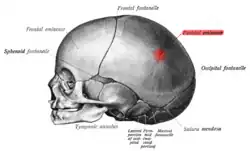

Skull of a new-born child from the side. (Parietal eminence shown in red.) | |

The parietal eminence (also parietal boss, parietal tuber, parietal tuberosity or tuber parietale) is a convex, smooth eminence on the external surface of the parietal bone of the skull. It is the site where intramembranous ossification of the parietal bone begins during embryological development. It tends to be slightly more prominent in men than in women, so may be used to help to identify the sex of a skull.[1]

Parietal eminence shown in red

Parietal eminence shown in red -